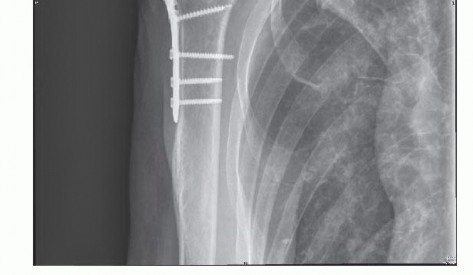

A history of fracture or extended immobilization should be elicited.

Previous surgeries including rotator cuff repair, capsular shift, Putti-Platt, Bristow-Latarjet, open glenoid bone grafting, and open reduction and internal fixation of a fracture should be documented as a potential cause of stiffness.

IMAGING AND OTHER DIAGNOSTIC STUDIES

Routine radiographic evaluation should include an anteroposterior (AP) view of the shoulder in neutral, internal, and external rotation as well as scapular Y and axillary lateral views.

Disuse osteopenia is often noted.

Concomitant findings may include calcific tendinitis or hardware signifying a previous surgical procedure (eg, open reduction and internal fixation, Putti-Platt) (

FIG 2

).

Magnetic resonance imaging (MRI) is obtained only if a rotator cuff tear or other soft tissue derangement is suspected.

We do not typically order an arthrogram or laboratory studies to confirm the diagnosis of adhesive capsulitis.

FIG 2 • Hardware on radiographs can be helpful in guiding treatment. In this instance, after treatment of a proximal humerus fracture with open reduction internal fixation, adhesions would be expected in the subdeltoid space.

4. ## Subacromial and Subdeltoid Bursoscopy

Subacromial and subdeltoid scarring and adhesions are common after prior rotator cuff repair and fracture fixation.

In cases of adhesive capsulitis, there is often a component of subacromial bursitis.

The subacromial space and subdeltoid space are always evaluated for bursitis as well as dense adhesions.